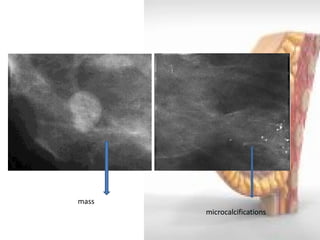

FINDINGS IN MAMMOGRAPHY

•DENSITY- Space occupying lesion seen in only

one projection

- no clinical significance

•MASSES- Space occupying lesion seen in two projections

Round or oval- benign

Irregular or lobulated- malignant

•CALCIFICATIONS – Malignant calcifications are usually<0.5mm, pleomorphic or heterogenous and grouped

mass

microcalcifications